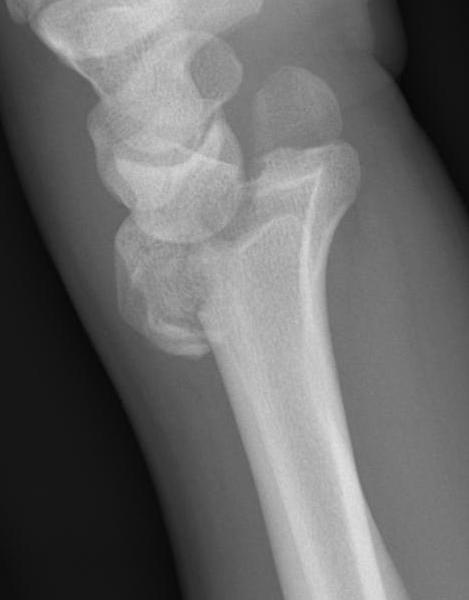

Distal radius fracture with shortening and dorsal tilt

Articular incongruency > 2 mm

Sigmoid notch disruption and DRUJ instability